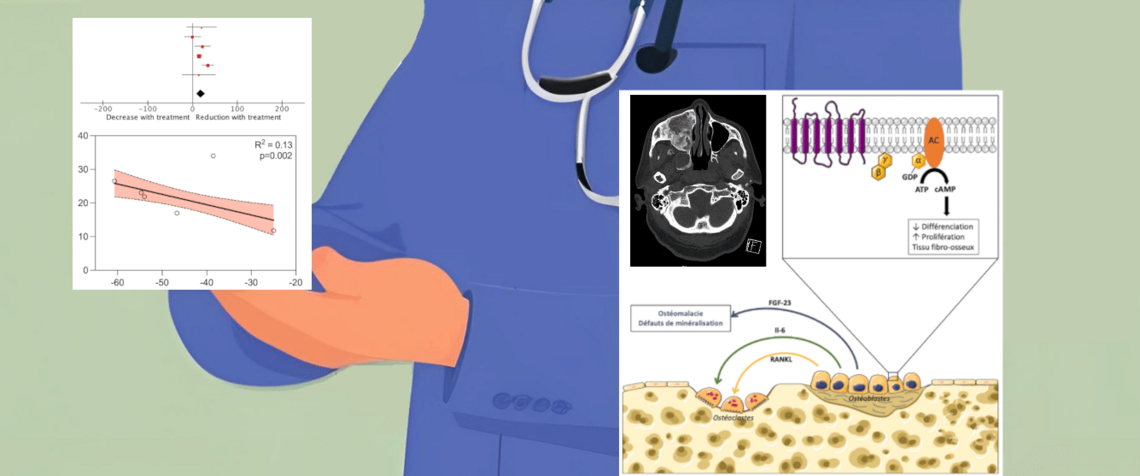

1. Je me posais la question de l’efficacité d’un traitement anti-ostéoporotique (les bisphosphates) dans la dysplasie fibreuse, une maladie rare qui fragilise les os des membres et du visage. En particulier je souhaitais évaluer l’effet de ces traitements sur la réduction de la douleur des patients puisque les études prises isolément étaient peu contributives.

2. Le processus de sélection des études a interrogé plusieurs bases de données médicales (la plus connue étant PubMed) à l’aide de mots clés et de filtres. Puis les études ont été classées selon des paramètres de qualité méthodologique, de population étudiée, ou encore selon l’existence de résultats complets ou non.

3. Une grande partie du travail a consisté en l’extraction des données des patients avant et après traitement soit sous la forme de moyennes soit sous la forme de données individuelles.

4. Puis ces résultats ont été combinés à l’aide d’un logiciel statistique en accès libre (Review Manager, groupe Cochrane, 2020). Il a été possible de mener différentes analyses dans plusieurs groupes de patients en résumant par exemple les effets chez les enfants, chez les adultes, selon les traitements utilisés, etc.

Ce travail a confirmé une efficacité de l’ordre de 32% sur la réduction de la douleur des patients traités. Néanmoins il faut garder l’esprit critique quant à l’interprétation des résultats : lorsque les études sont de mauvaise qualité, les résultats de la méta-analyse le sont aussi, étudier l’effet d’un médicament sur des études avant-après ne vaut pas de comparer ce traitement au placebo. Enfin il est d’usage en médecine de ne pas publier des résultats négatifs, or la publication de ce type de résultats pourrait alimenter les méta-analyses et fournir des conclusions plus robustes. Fort de cette expérience je suis maintenant capable d’appliquer cette méthode dans ma discipline pour comparer des techniques chirurgicales, ou encore analyser des complications chirurgicales même rares.